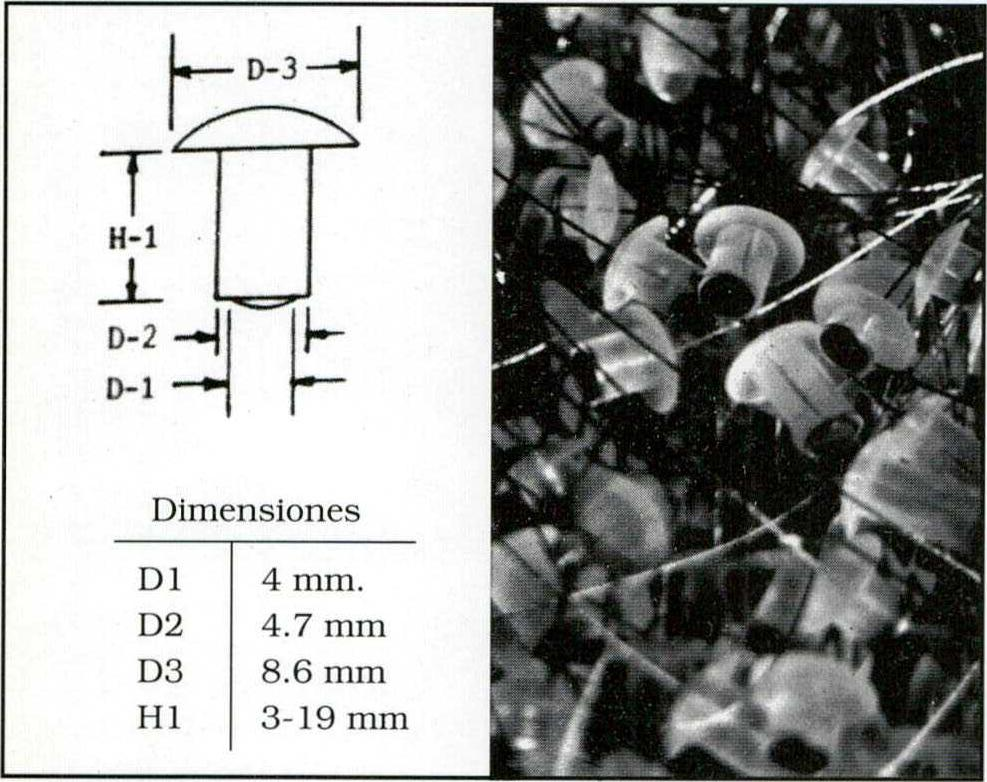

En algunos casos se utilizaron PEG2 o tiras de electrodos epi o subdurales. En todos los casos se confirmó la lateralidad presupuesta (Fig 2).

Fig. 2. Los PEG son "tapones" o tornillos uno de cuyos extremos (contactos) se apoya en la duramadre